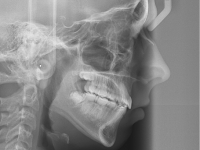

El paciente D.M. llega a nuestra consulta sin los 2 premolares inferiores que le quitaron en anteriormente para empezar a mejorar el caso.

– Perfil plano

– Clase III esquelética

– Clase III dental

– Apiñamiento superior muy importante

Fotos antes de tratamiento: